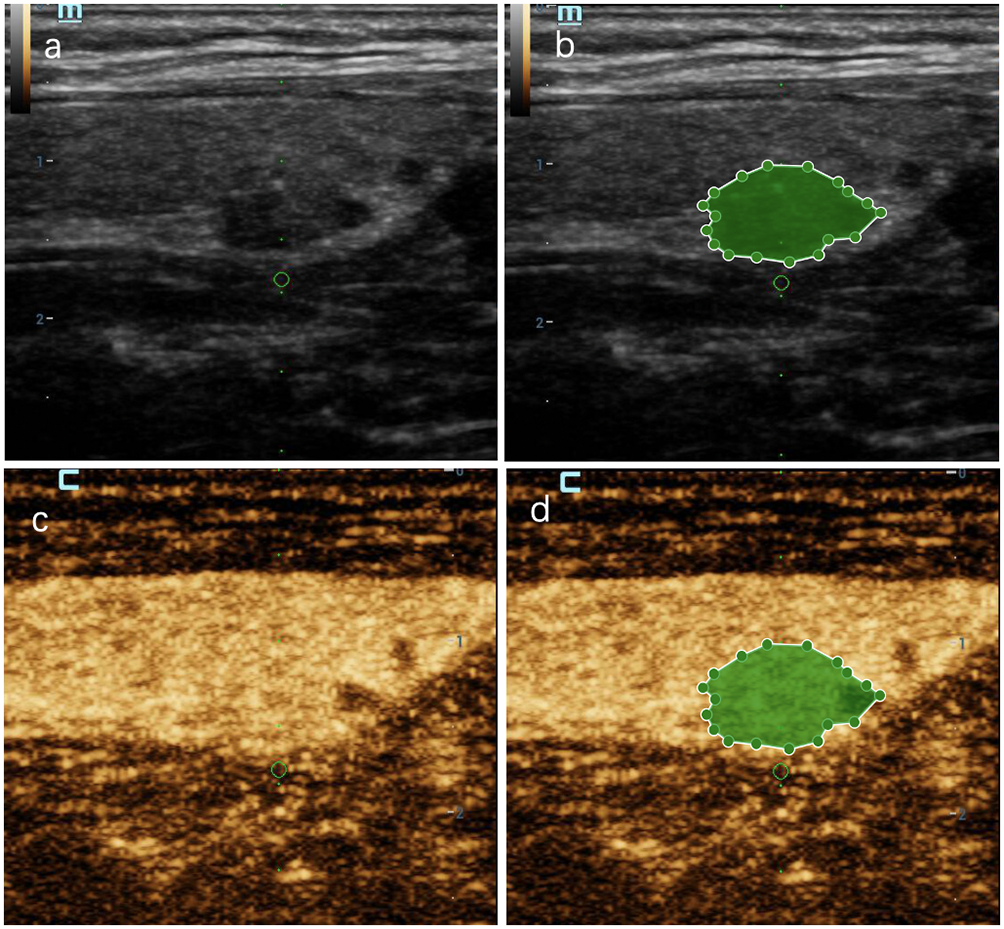

Figure 7

A thyroid nodule in left lobe in a 46-year-old woman in test cohort. (A) 2D-US image; (B) the mask image corresponding to 2D-US image; (C) CEUS image at peak time; (D) the mask image of CEUS image at peak time. The nodule was solid, hypoechoic, blurred margin, aspect ratio less than 1, with microcalcification and was categorized as C-TIRADS 4c. CEUS showed “later wash-in, heterogeneous enhancement” and “later wash-out”, and was diagnosed as malignant. RF model classifies it as malignant. Histologic analysis revealed papillary microcarcinoma (PTMC).